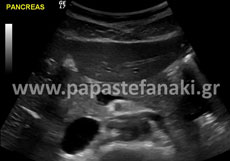

Τα όργανα που ελέγχουμε είναι το ήπαρ, η χοληδόχος κύστη, το πάγκρεας, οι νεφροί, ο σπλήνας, ο οπισθοπεριτοναϊκός χώρος, το έντερο και τα τοιχώματα της κοιλίας.